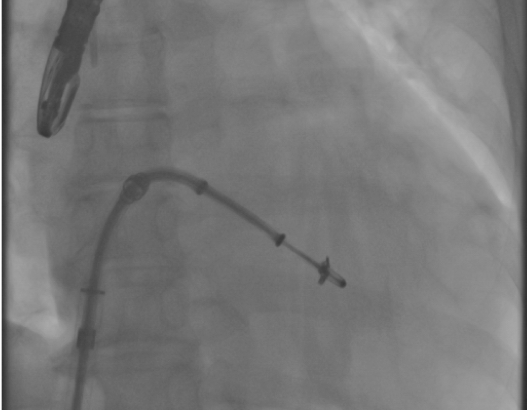

- これまでは外科手術が困難で治療を受けることができなかった方を対象として、より低侵襲なカテーテルによるアプローチで僧房弁の修復を行う治療です。

- 人工心肺が必要の無い僧帽弁形成術

- 拍動下でのリアルタイムな僧帽弁逆流の評価が可能

- 僧帽弁逆流が最大限消失する場所への弁尖把持が何度でも施行可能